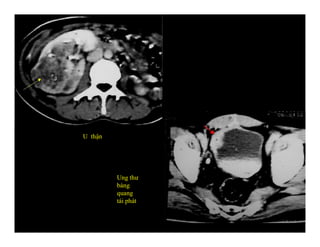

U thận

Ung thư

bàng

quang

tái phát